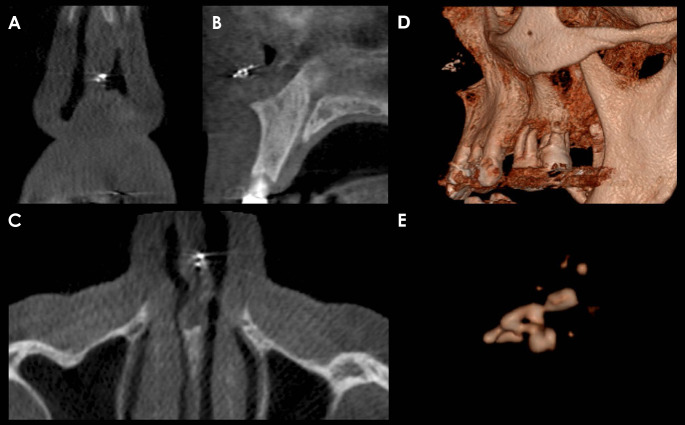

Nasal myiasis is an infestation by dipterous larvae within the nasal cavity, where they feed on both living tissue and fluid. This condition predominantly occurs in rural areas of tropical countries, where inadequate sanitation and a hot, humid climate create an ideal environment for larvae development. A 57-year-old, otherwise healthy male rural worker presented with a toothache in the region of the maxillary incisors. Imaging studies identified a punctiform radiopaque/hyperdense area near the nasal septum in the left nasal fossa. The larva was surgically excised and sent for histopathological analysis. Histologic sections confirmed the clinical diagnosis, and the patient remained asymptomatic after a 2-month follow-up. Nasal myiasis can mimic the symptoms of a toothache in the anterior region of the maxilla. This condition can affect even immunocompetent patients, and complementary imaging studies may be decisive in diagnosing it.